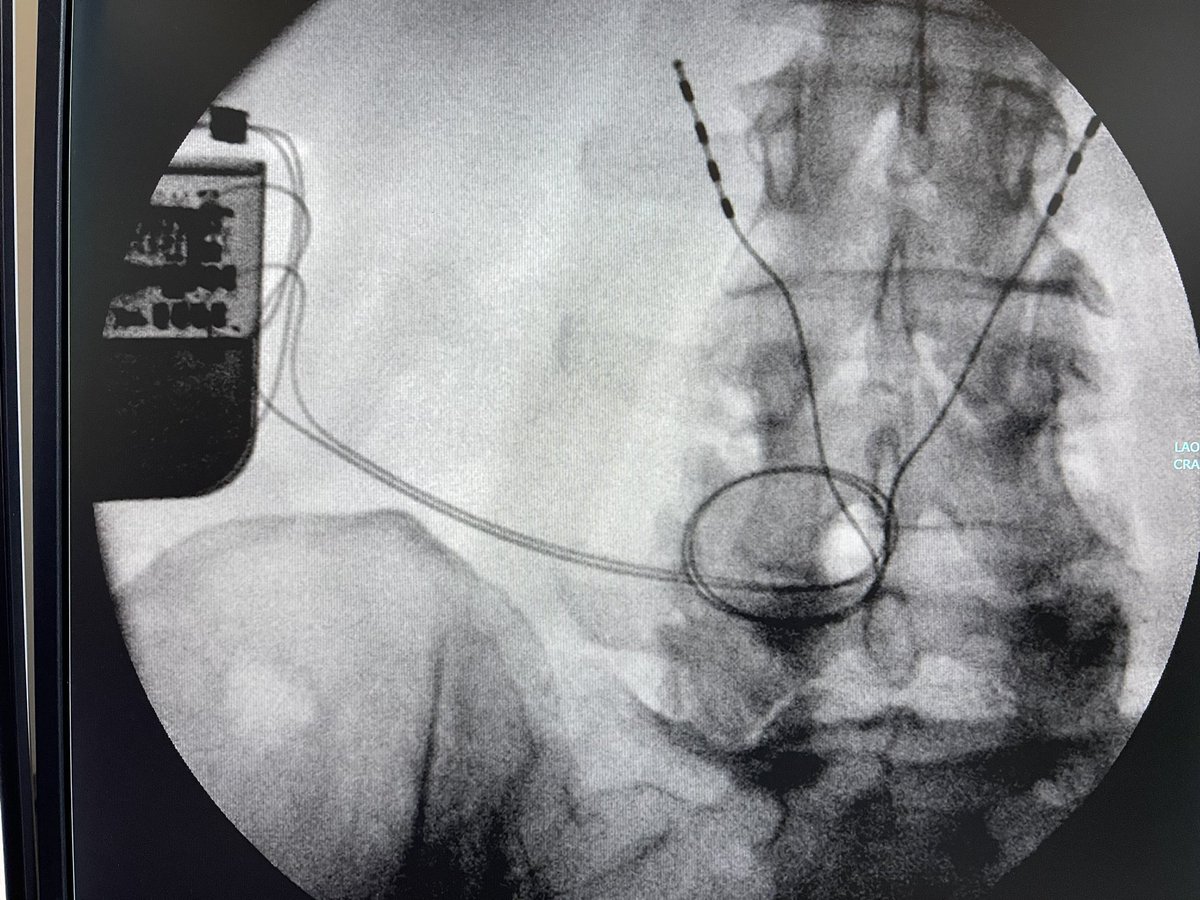

So, this is some real talk regarding #MSKIR in the real world.

@TheStrykerIVS makes a great product, #SpineJack, that shows up in a lot of cool posts on this and other platforms.

This example was just posted by @neuroradiology - a great example of the genre.